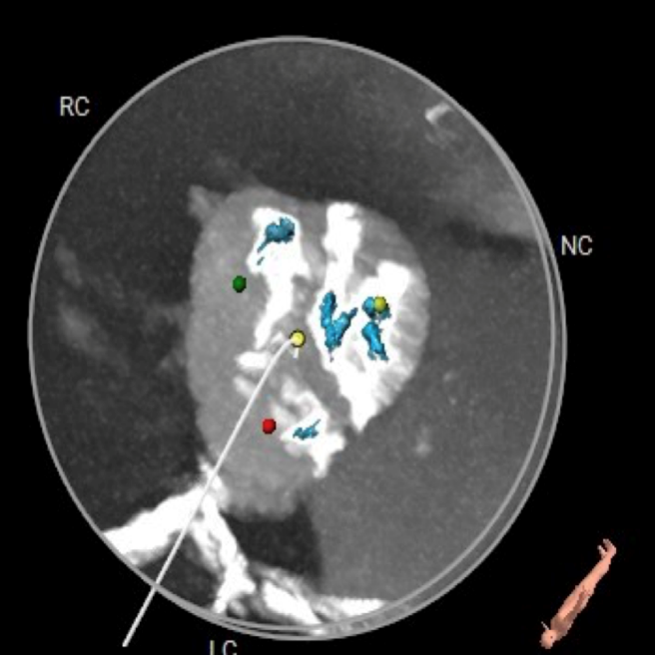

CT数据显示该患者为三叶式主动脉瓣。

主动脉瓣瓣环周长66.2,平均周长径 21.1mm,SOV:32.2mm*36.4mm*34.1mm,瓣叶增厚,瓣上钙化分布不均,主动脉瓣环水平夹角67度,横位心。

钙化分布